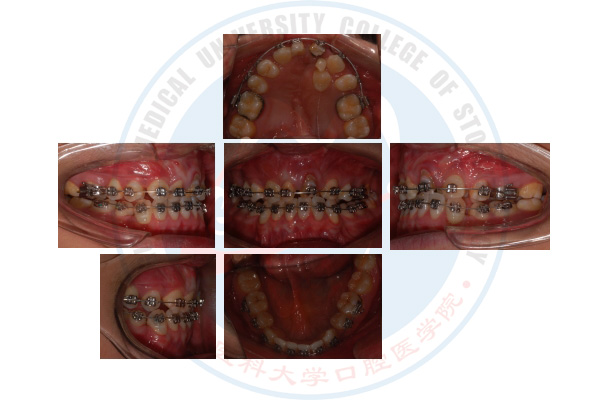

唇腭裂序列治疗之正畸治疗

正畸治疗前

正畸治疗中

正畸治疗后